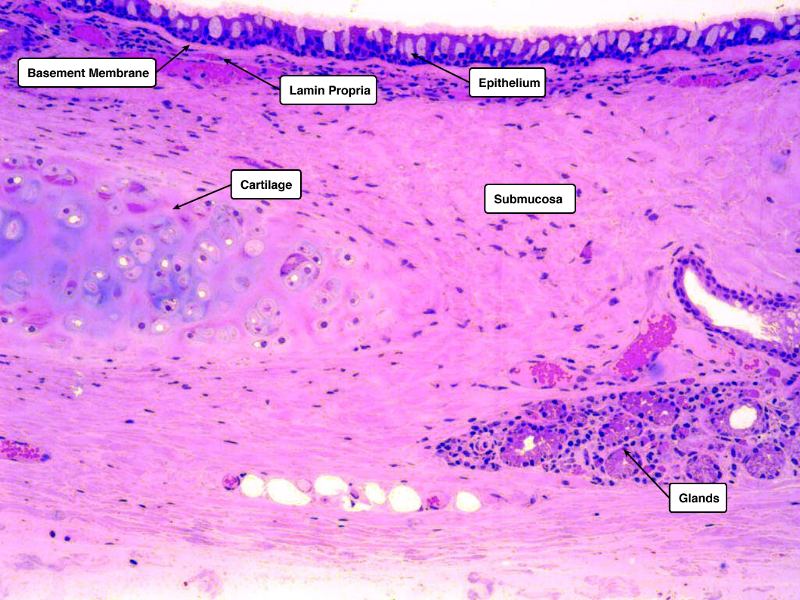

Identify and describe the epithelium on the following slide:

Pseudostratified columnar epithelium

What cells are present?

• Goblet cells

• Basal cells

• Ciliated columnar cells

• Unciliated columnar cells